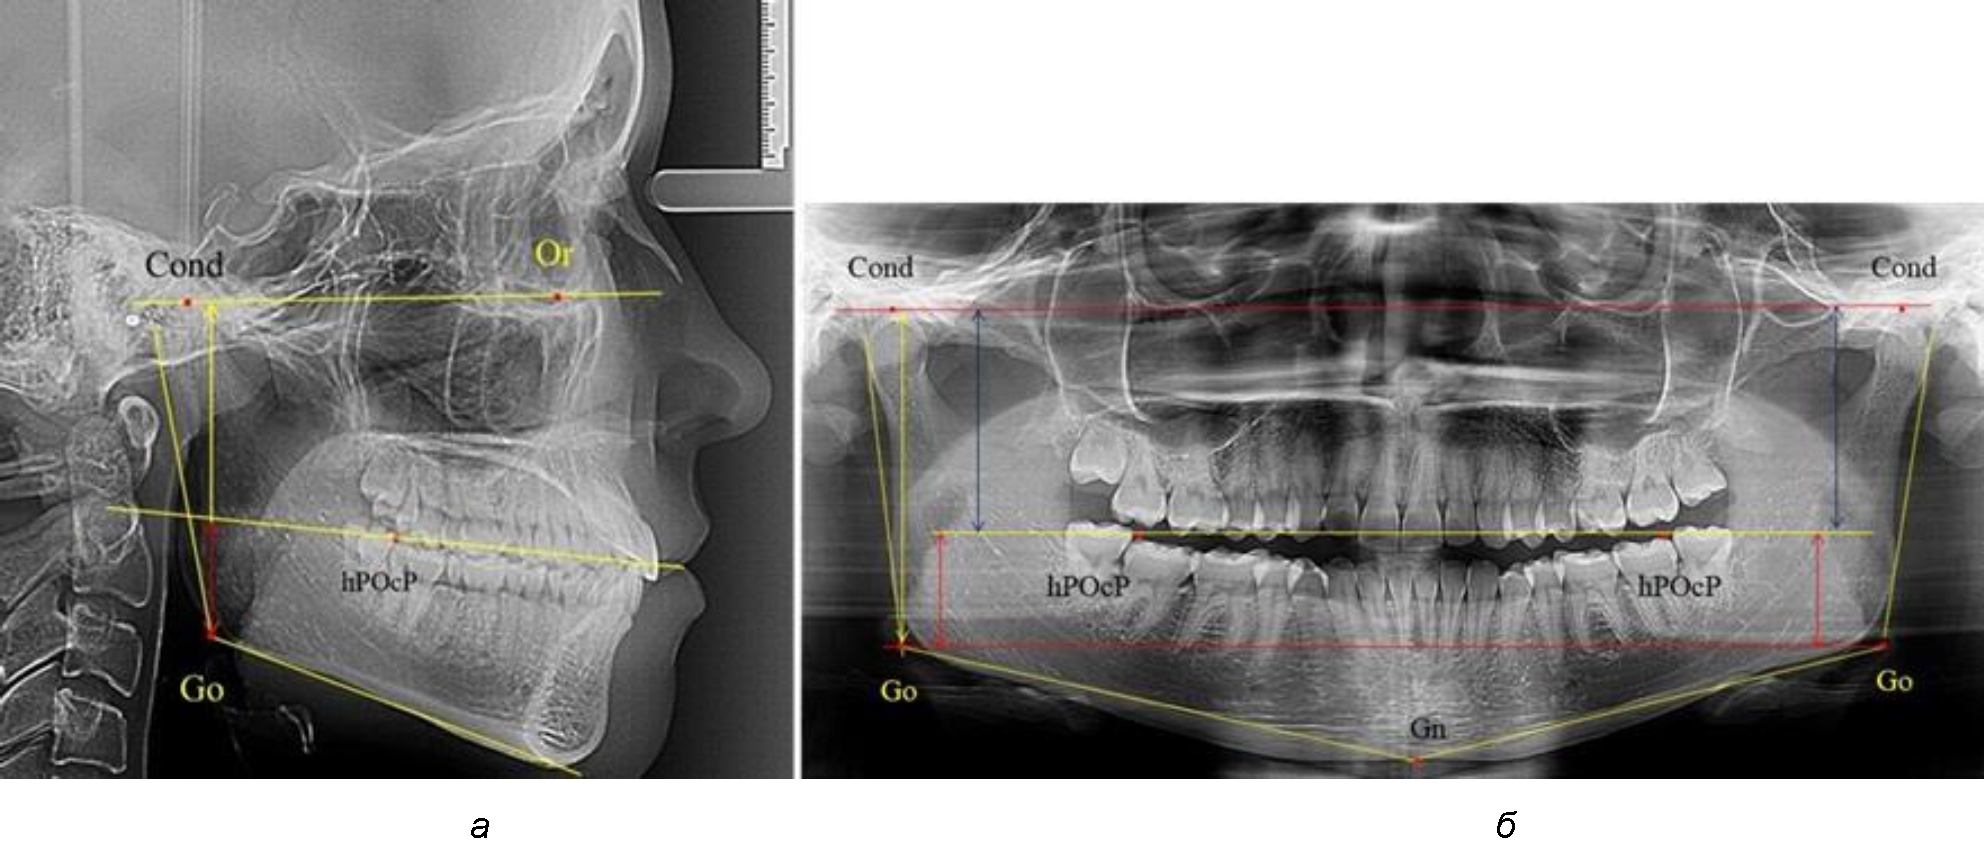

Рис. 1. Метод измерения высоты ветви нижней челюсти на телерентгенограмме (а) и ортопантомограмме (б)

В 1-ю подгруппу были включены 36 комплектов телерентгенограмм и ортопантомограмм [или (48,65 ± 5,81) % от общего количества], на которых средняя величина отношения верхней части ветви к нижней составляла 1,95 ± 0,03, что соответствовало показателям, полученным по группе в среднем, но с меньшим показателем ошибки среднего значения. Визуально верхняя окклюзионно-суставная часть выглядела вдвое больше нижней окклюзионно-гониональной (рис. 2). При этом высота ветви составляла (62,09 ± 1,22) мм. Максимальная высота была 71 мм, а минимальная – 55 мм. Высота верхней части составляла (41,02 ± 0,77) мм, а высота нижнего отдела ветви была (21,09 ± 0,51) мм.

Рис. 2. ОПТГ пациента 1-й группы с оптимальным коэффициентом соотношения частей ветви нижней челюсти

Рис. 3. ОПТГ пациента 2-й группы с уменьшенным коэффициентом соотношения частей ветви нижней челюсти